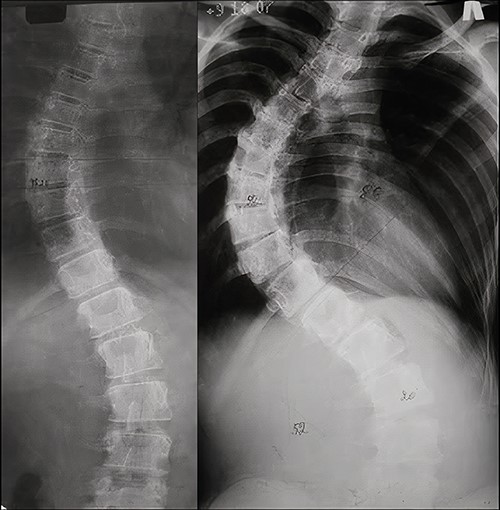

On 10-year follow-up, radiographs of the spine in the standing position in 2021 adequate correction are preserved with a slight asymptomatic increase of lumbar deformity (Figs 4 and 5).

X-rays of the patient’s spine at a 10-year follow-up. (a) AP X-ray of the spine in standing position. There is a slight increase in the lumbar curve. (b) Lateral X-ray of the spine in standing position.